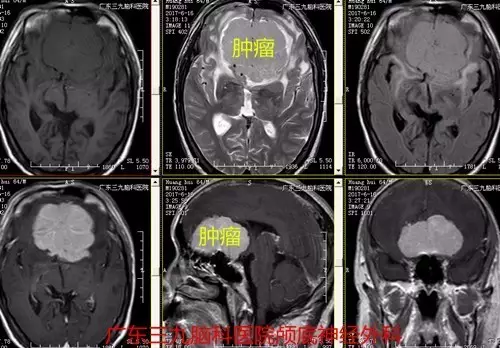

图2:术前磁共振提示肿瘤位置、大小约5.9×6.3×3.5cm

本例患者为老年男性,病程长,以头晕头痛就诊,伴恶心呕吐,未有明确定位症状,易误诊,行头颅CT及MR检查提示前颅窝底脑膜瘤。临床辅助检查中,头颅MR扫描对前颅窝底脑膜瘤的诊断意义最大。MRI 检查不仅可以显示肿瘤的体积及具体起源部位,而且还可以清楚显示肿瘤与邻近重要结构,如视神经、颈内动脉及其分支、垂体柄、下丘脑等的关系,这对指导手术人路的选择具有重要的意义。多数情况下前颅窝底脑膜瘤的MR增强扫描可见较均匀一致的强化,这与脑膜瘤的血运较丰富有关,有的情况下,如果肿瘤增强十分明显,而且肿瘤瘤内或周边有较多的血管流空,多提示肿瘤的供血血管较多,肿瘤血运丰富。本例患者术前CTA提示其内血供丰富,双侧大脑前动脉受压明显向右侧偏移,MR增强明显,其内见较多流空影,大小约5.9×6.3×3.5cm,体积巨大,且与嗅沟、视神经、垂体炳、下丘脑等关系密切,手术难度较大,术中行冠状切口经额予以全切除,切除时间约半小时,术中出血少,术后患者恢复快,术后严格监测血离子、尿量、垂体激素等的变化,术后患者出现一过性精神症状,目前恢复良好出院。